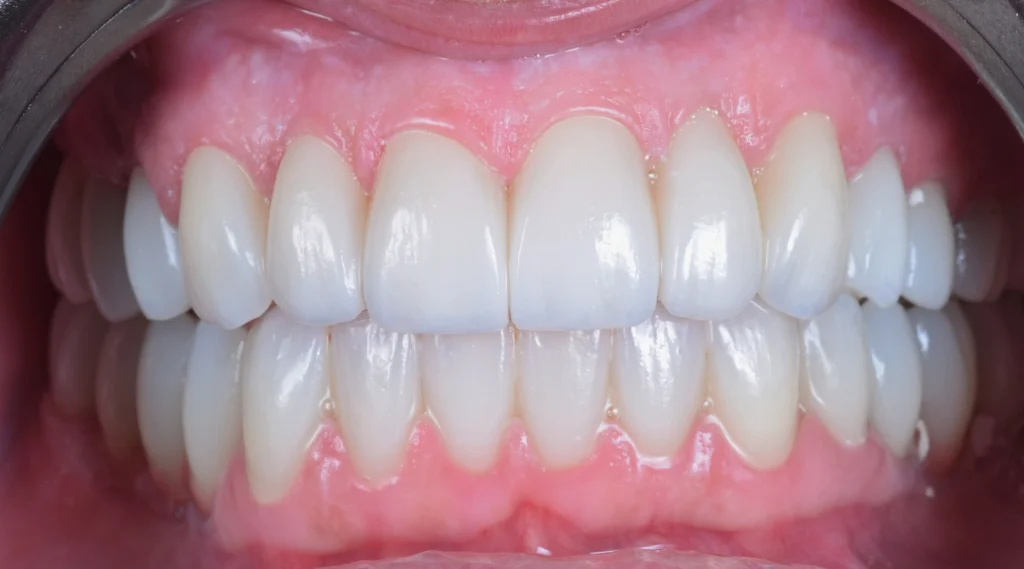

After the healing period of 6 months, the teeth were prepared and a prototype smile with provisional teeth was placed. After the analysis of the prototype smile, we made all the changes need to provide this patient with this new beautiful smile with zirconia crowns and bridges over the dental implants.

All of this was made with a digital workflow.

The patient left our clinic smiling and very happy for her new smile. This life changing cases is what we work for, it is what we live for.Â